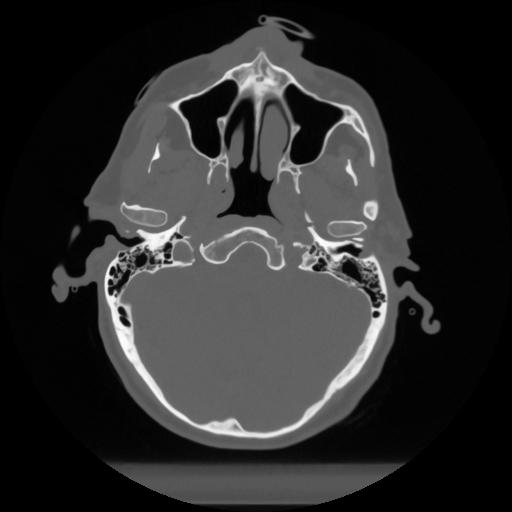

12 P.BLANDAS,,Vol,0.5,P.BLANDAS,,